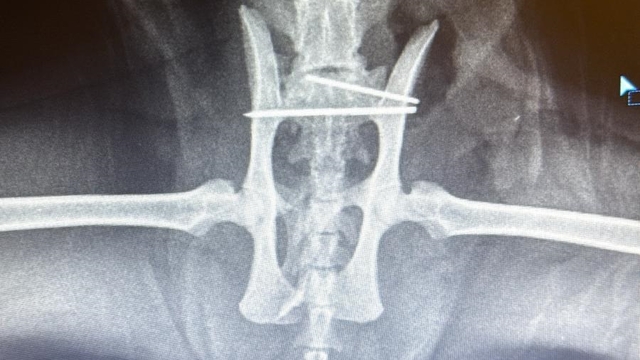

Merkez ilçeye bağlı Nene Hatun Kız Mesleki ve Teknik Anadolu Lisesi bahçesinde öğretmenlik yapan Ülkü Yılmaz, yürümekte zorluk çeken kediyi alıp veterinere götürdü. Veteriner hekimler tarafından yapılan ilk müdahale sonrasında, röntgen filmi çekilen kedinin kalçasının kırık olduğu tespit edildi. Öğretmenlerin verdiği maddi destekle Avanos Terapi Veteriner Kliniği’nde ameliyat edilen kedi, 2 haftanın sonunda sağlığına kavuştu. Tedavisi tamamlanan kediyi, okul öğrencilerinden Azra Edepli sahiplendi.